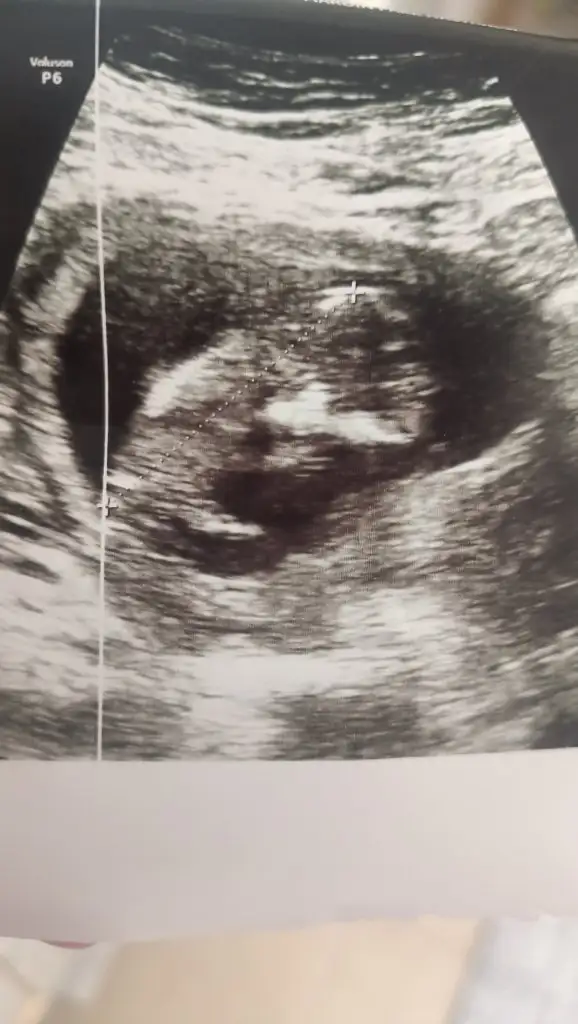

Kızlar doktordan geliyorum sata göre 16+5haftalik ultrasona göre 19+2 haftalık artık olasılıklara mahal vermeden kesinlikle kızım oluyor Mergül Şifa geliyor listeye ekleyebilirsiniz :KK25: